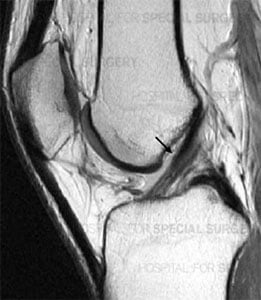

Side-view MRI showing a healthy, intact ACL.